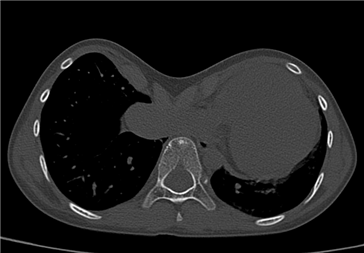

漏斗胸外观 漏斗胸CT示压迫心肺